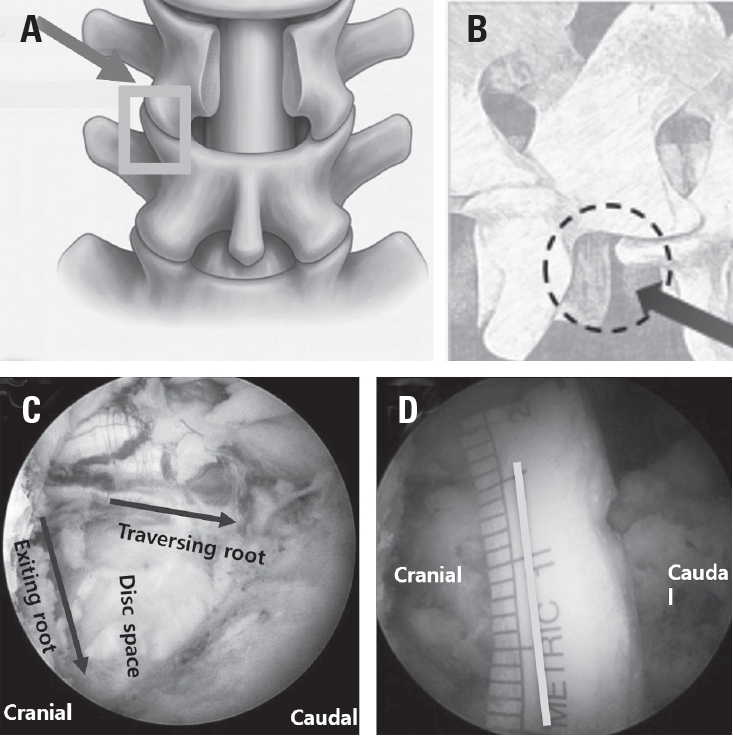

Under anteroposterior fluoroscopic guidance, the pedicles and transverse processes at the target level were marked. Two vertical skin incisions approximately 2 cm lateral to the pedicle line were created to establish the viewing and working portals. At the L5–S1 level, the portals were positioned more cranially to avoid iliac crest interference. When endplate visualization was anticipated, additional medial portals (M portal) were created to accommodate the endoscope or a root retractor during cage insertion (Fig. 1).

Portal placement and fluoroscopic landmarks for biportal endoscopic revision extraforaminal lumbar interbody fusion (BE-REFLIF).

Surgical incisions for BE-EFLIF using multiportal approach. P+2 ports mean that it is made 2 cm lateral to the pedicle lateral margin, and are used for facetectomy and foraminotomy. Based on when a right-handed surgeon performs a left side approach, the port on the left used as a viewing port is called P+2 (L) port, and the port on the right used as a working port is called P+2 (R) port. Additional M ports are made to perform Root retraction during cage insertion or accomodate the endoscope. BE-EFLIF, biportal endoscopic extraforaminal lumbar interbody fusion